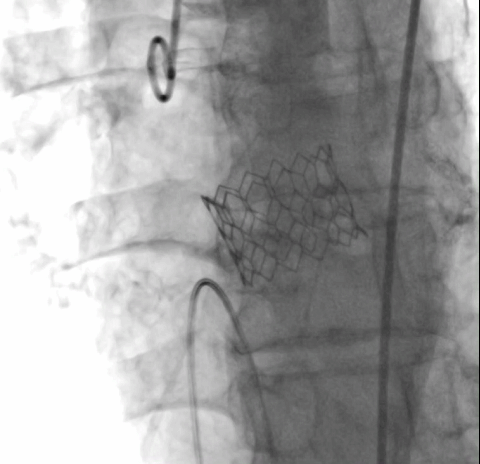

经详尽影像学重建、评估及病例讨论,决定选择经右侧股动脉为主入路,跨瓣成功后先以23#球囊预扩张满意,后植入25# Renatus球扩式介入主动脉瓣,再以24#球囊后扩。手术耗时约1小时,患者全程生命体征平稳,出血极少。介入主动脉瓣植入位置理想,功能表现出色,造影及TEE观察仅轻微瓣周漏,无中央性反流,主动脉瓣峰值流速及平均跨瓣压差分别降至2.3m/s和8mmHg,未发生传导阻滞和冠脉异常。

瓣膜释放 主动脉根部造影